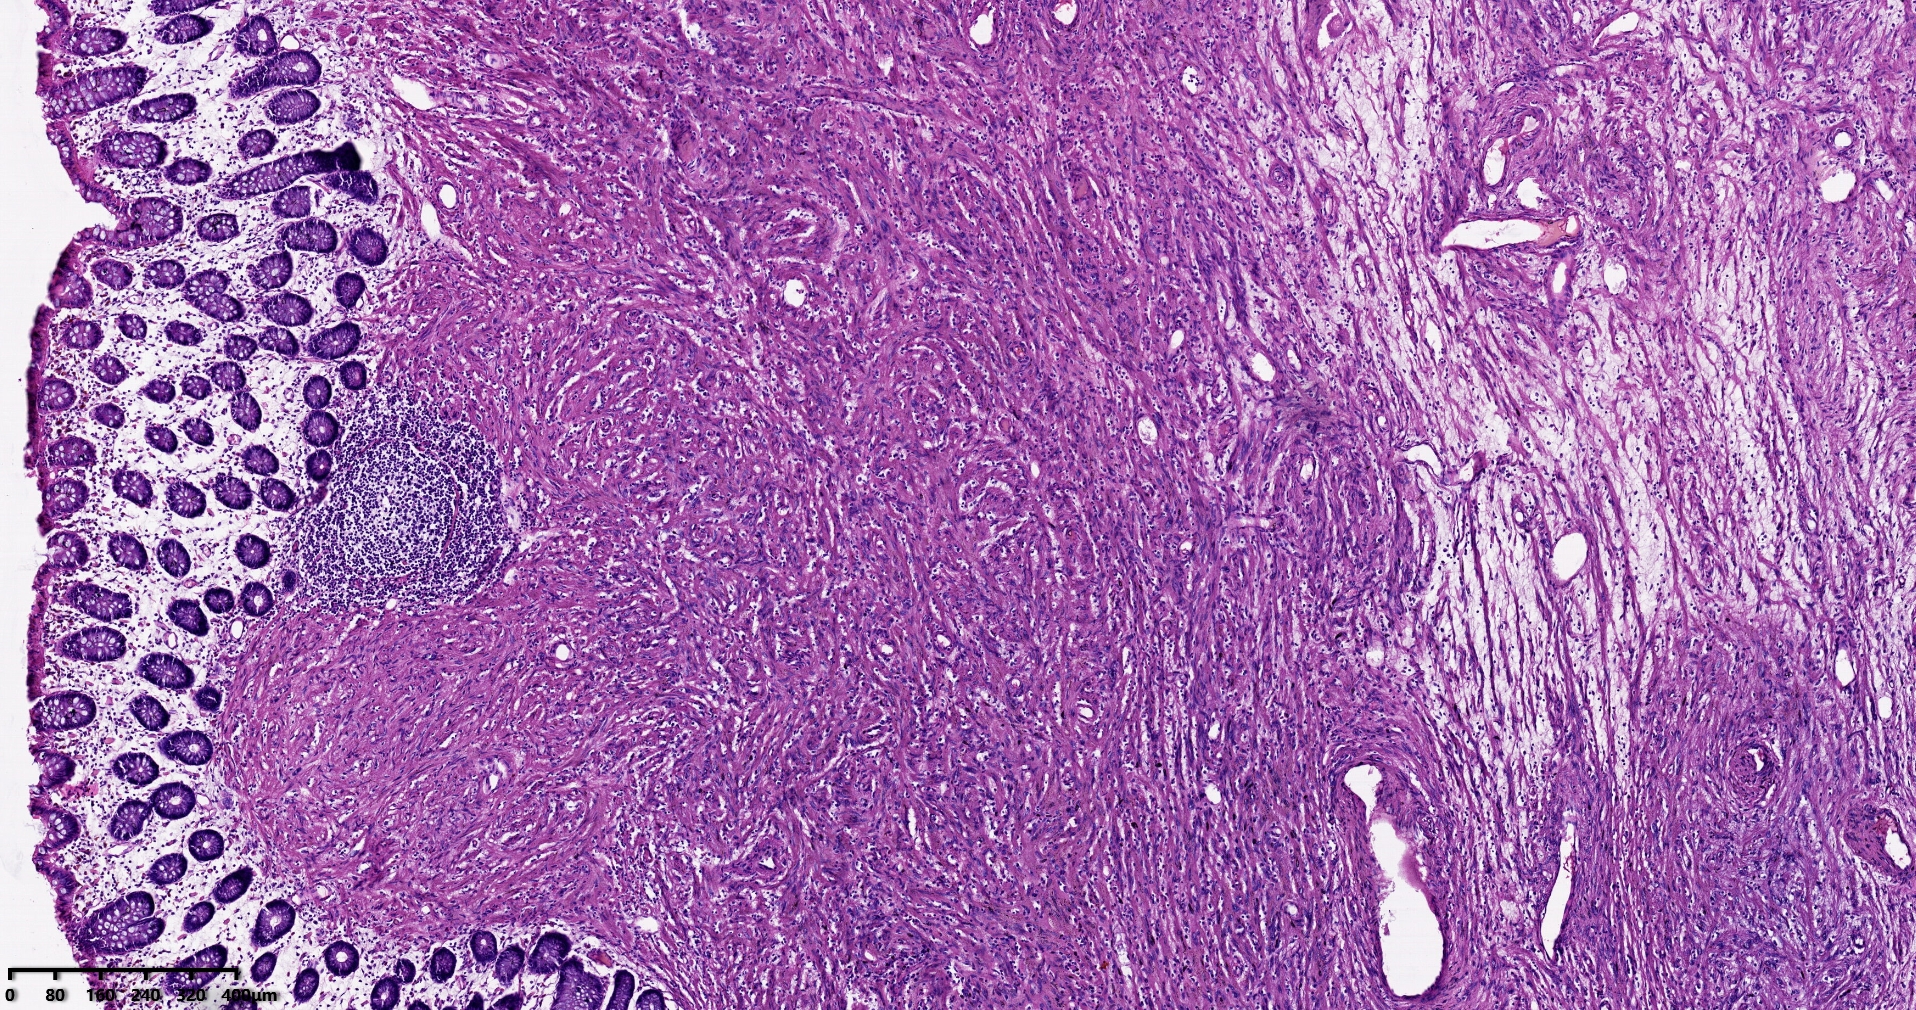

结肠肝曲息肉状肿物,平滑肌瘤?胃肠道间质瘤?炎性纤维性息肉?

性别

男

年龄

56岁

临床诊断

结肠肝曲息肉

一般病史

不详

标本名称

大体所见

灰红色椭圆形息肉一个,直径2.5cm,蒂长0.5cm,切面灰白灰红色,质中。

请路过的老师指教。

考虑间质瘤?

就HE形态而言,间质瘤的可能性要大一些,建议做免疫组化协助鉴别。